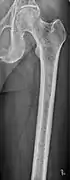

Medical imaging

The diagnostic examination of a person with suspected multiple myeloma typically includes a skeletal survey. This is a series of X-rays of the skull, axial skeleton, and proximal long bones. Myeloma activity sometimes appears as "lytic lesions" (with local disappearance of normal bone due to resorption) or as "punched-out lesions" on the skull X-ray ("raindrop skull"). Lesions may also be sclerotic, which is seen as radiodense.[70] Overall, the radiodensity of myeloma is between −30 and 120 Hounsfield units (HU).[71] Magnetic resonance imaging is more sensitive than simple X-rays in the detection of lytic lesions, and may supersede a skeletal survey, especially when vertebral disease is suspected. Occasionally, a CT scan is performed to measure the size of soft-tissue plasmacytomas. Nuclear Medicine Bone scans are typically not of any additional value in the workup of people with myeloma (no new bone formation; lytic lesions not well visualized on nuclear bone scan).